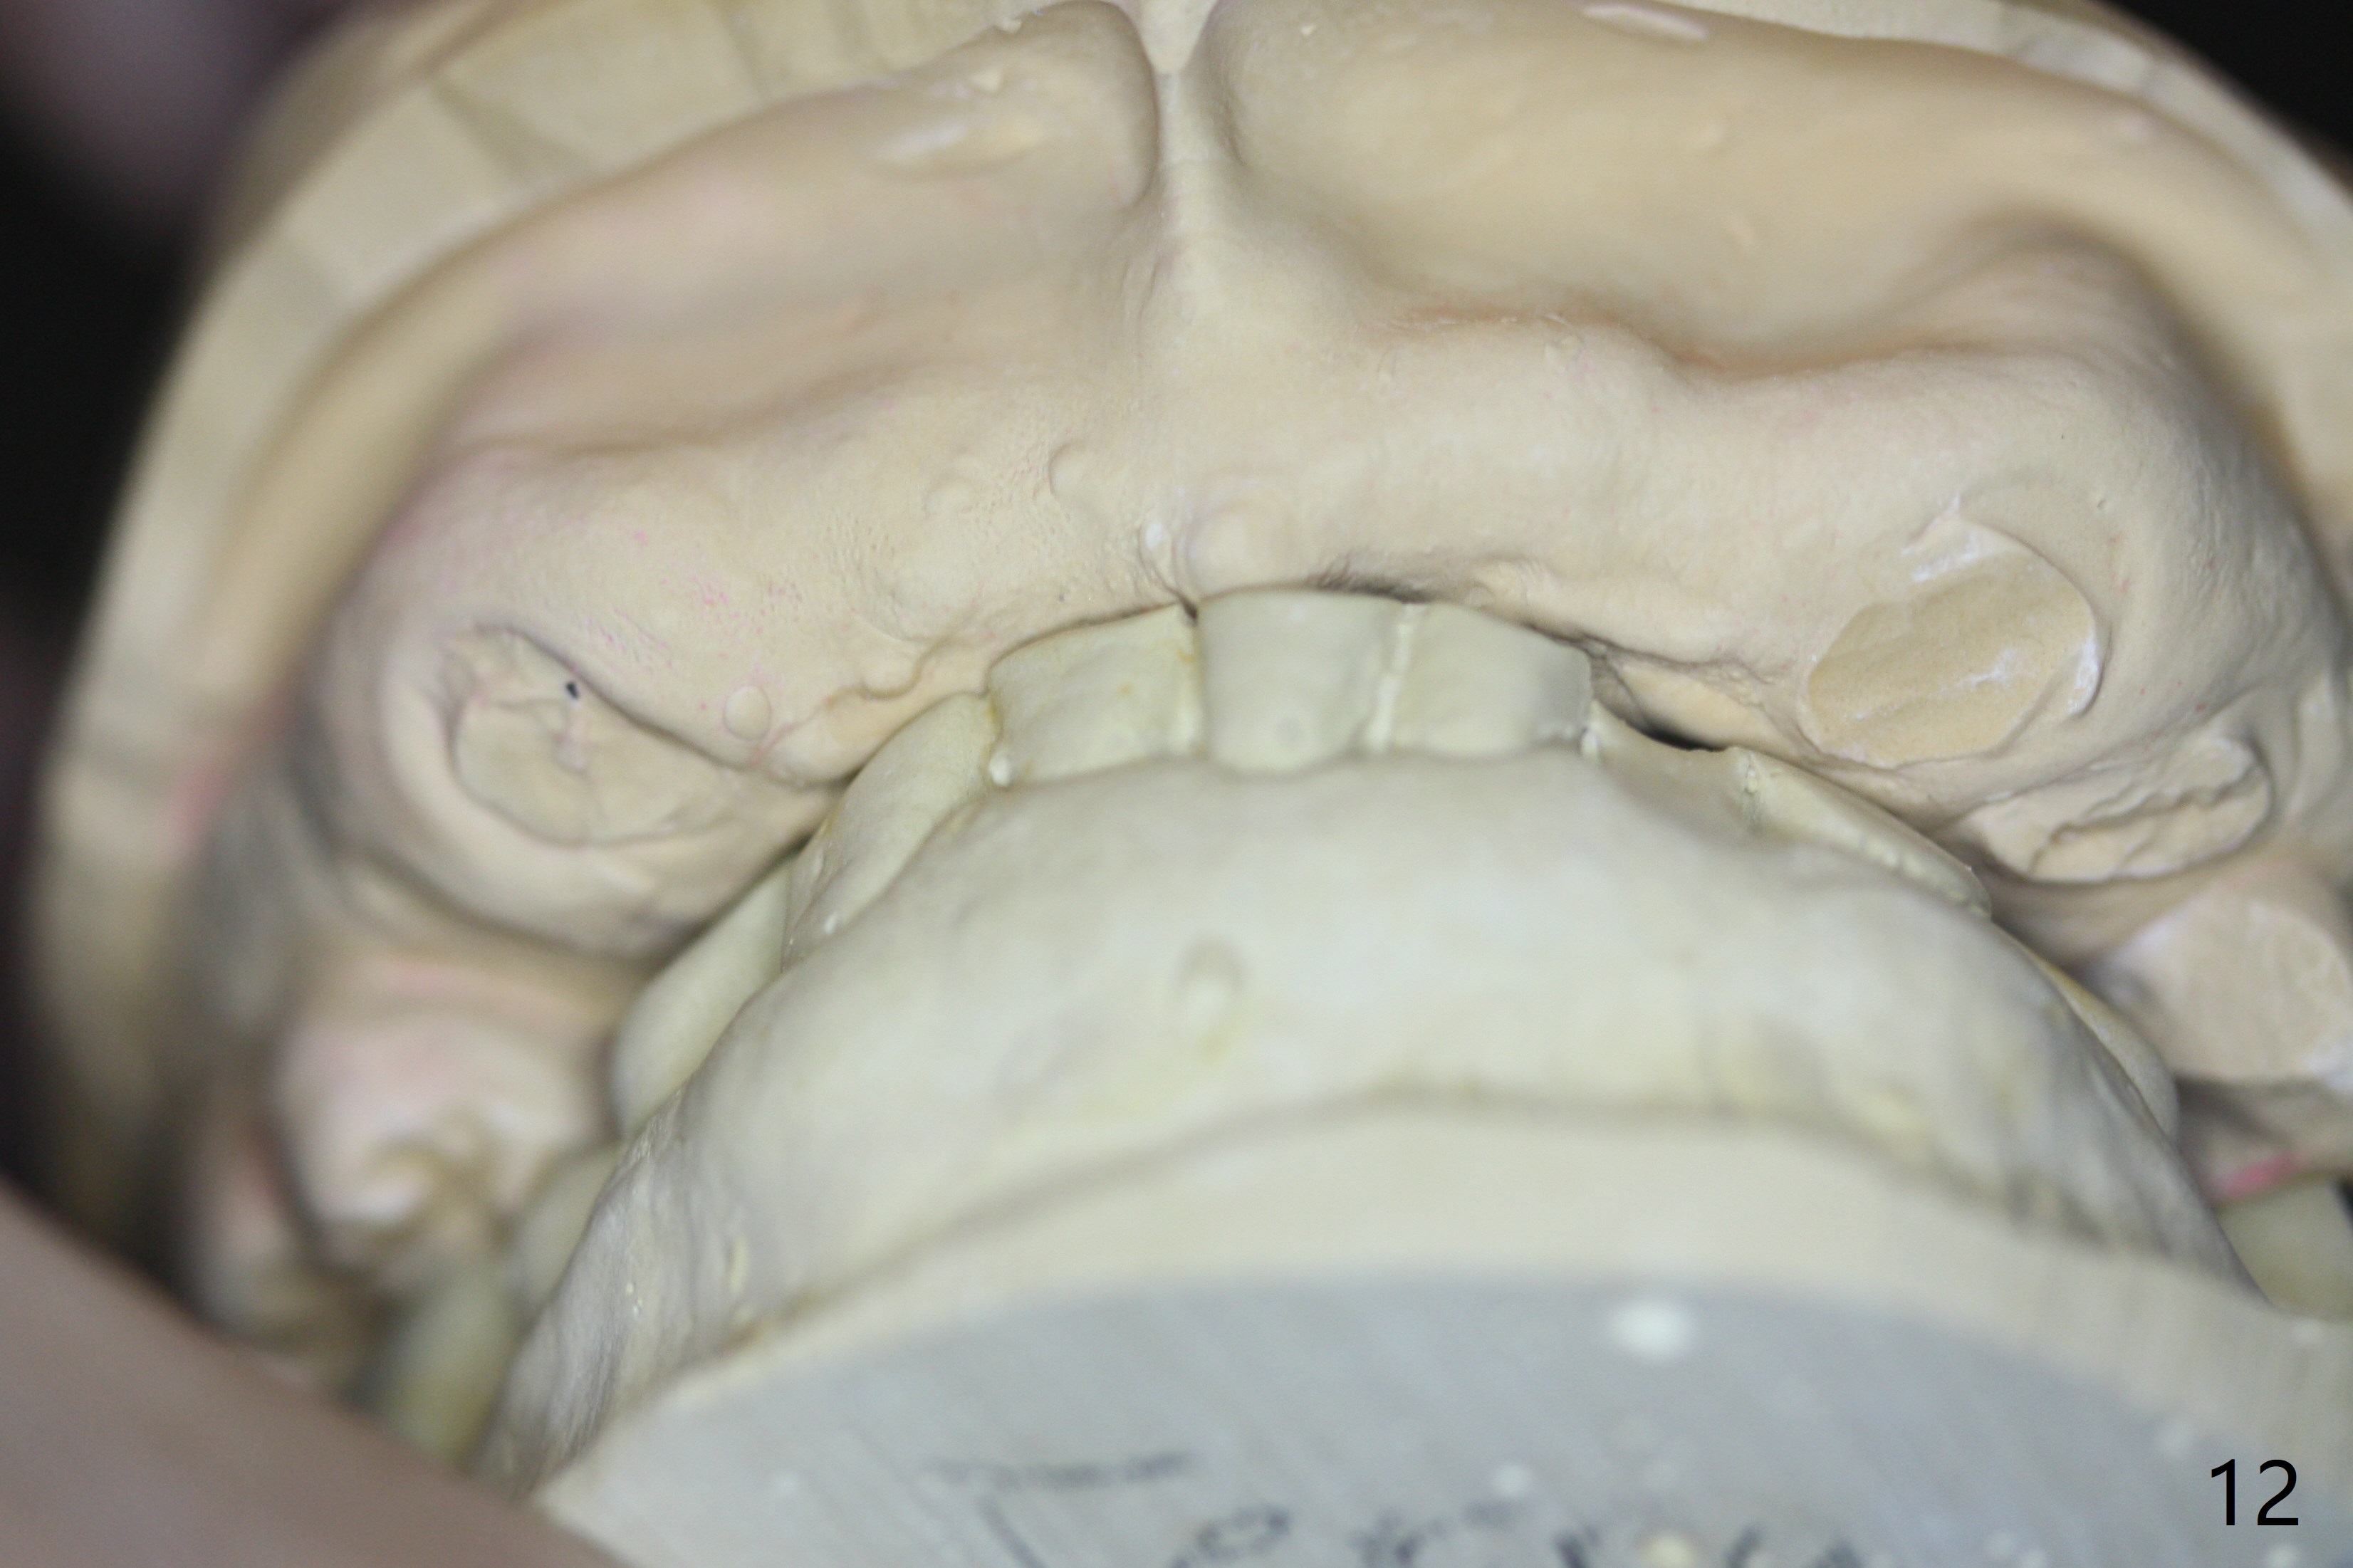

It is smooth and quick to finish osteotomy with guide at #6,7,10-12, but when 3 mm 1-piece implants are placed free hand at #7 and 10 (Fig.1,2), the gingival parts of the abutments contact the incisal edges of the lower incisors (anterior deep bite) in spite of effort to change the trajectory by repeated back and forth placement after use of Lindamann bur buccally. Following an immediate provisional (Fig.3,4), the occlusal surface of the posterior teeth are raised to eliminate anterior restoration interference. Immediate postop CBCT shows that the implants at #7 and 10 could be placed more buccally (Fig.6,7, as compared to the normal position at #6,11,12 (Fig.5,8,9)). Fig.10 was taken 2 days preop, while Fig.11-13 postop. Can we change 1-piece implants (3mm) at #7 and 10 to 2-piece one (3.5) and use angled or cementation abutments for easy restoration (Fig.14-16)?